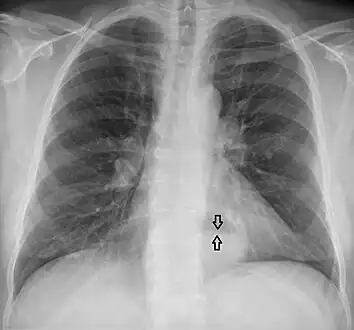

- A large hiatal hernia on chest X-ray marked by open arrows in contrast to the heart borders marked by closed arrows

This hiatal hernia is mainly identified by an air-fluid level (labeled with arrows).